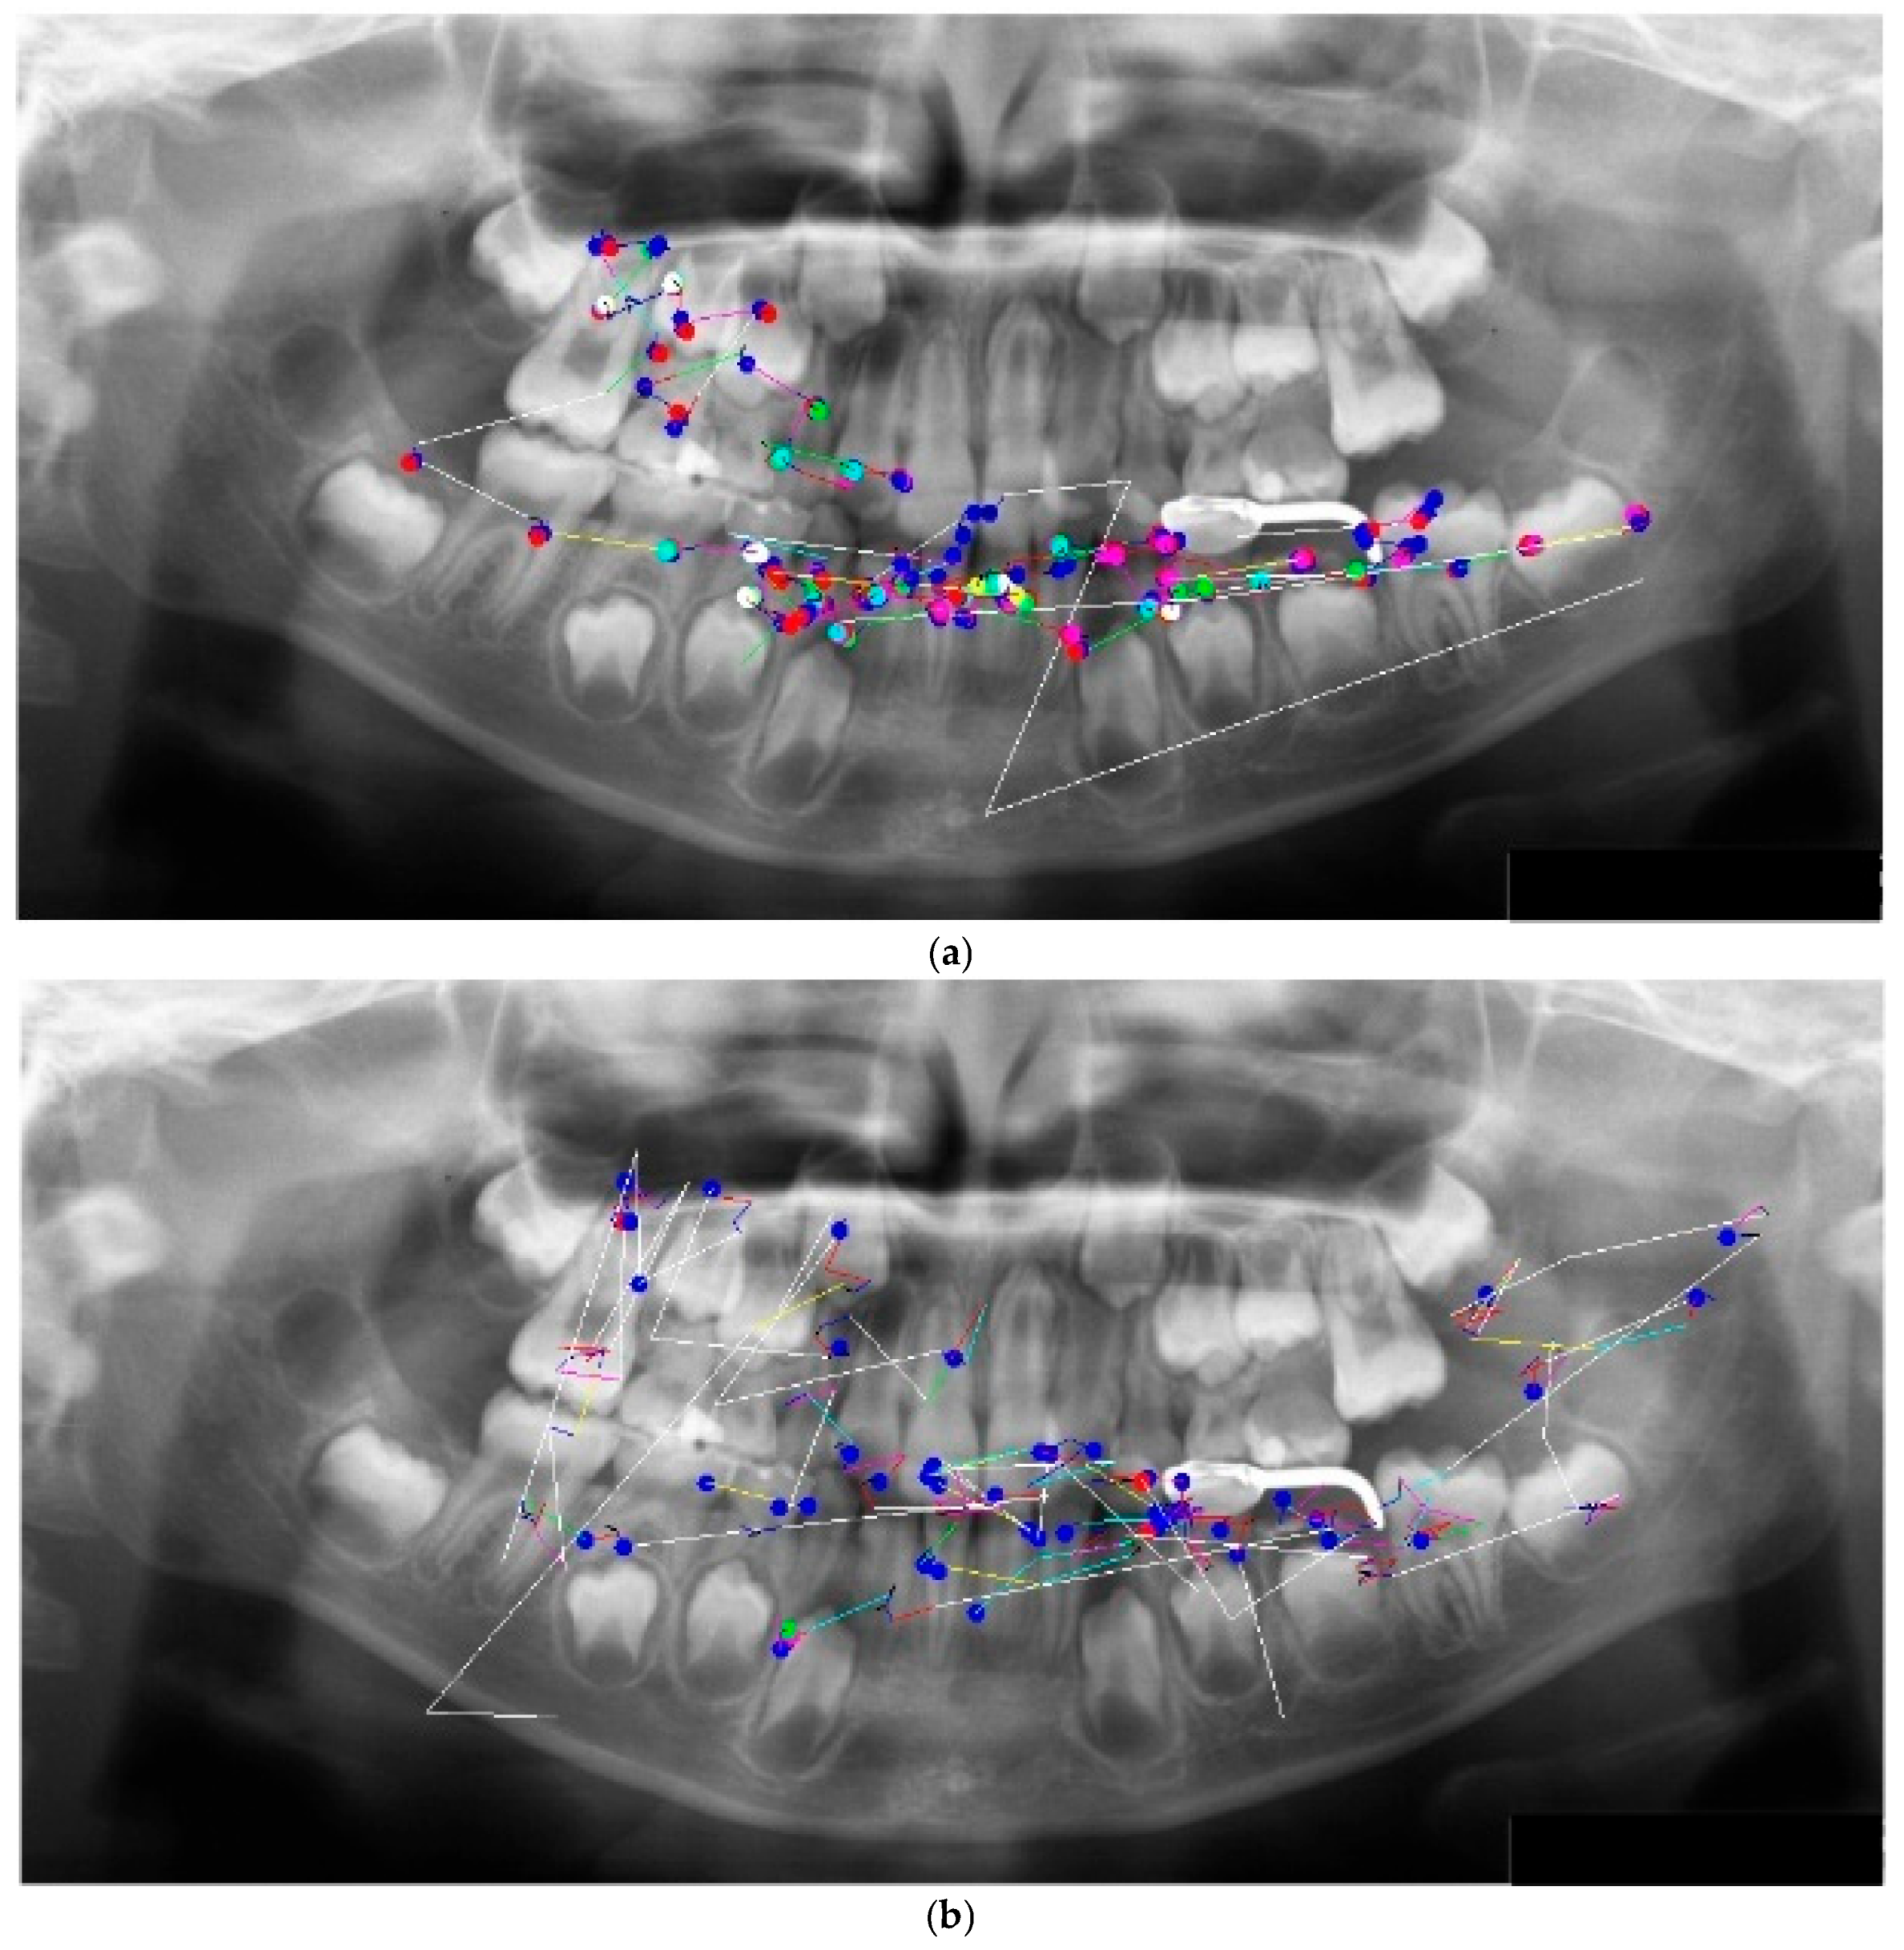

A PAN of a mixed dentition case (Hellman’s dental age IIIA, without congenital absence) was used as the test image. The radiograph revealed three specific findings: a maxillary inverted impacted supernumerary tooth, space maintainer, and restoration (Figure 1). Each participant was instructed to interpret the image and informed that it would be displayed until they indicated that their interpretation was complete. All participants completed radiology coursework and were undergoing clinical training at the time of the study.

Figure 1. Test image.